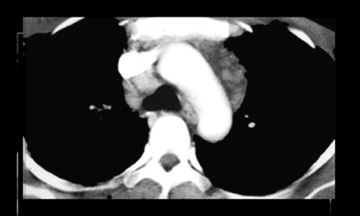

Computed tomography shows para-aortic and retrocaval lymphadenopathy. CT can demostrate enlarged lymph nodes which are not visible on radiographs. |